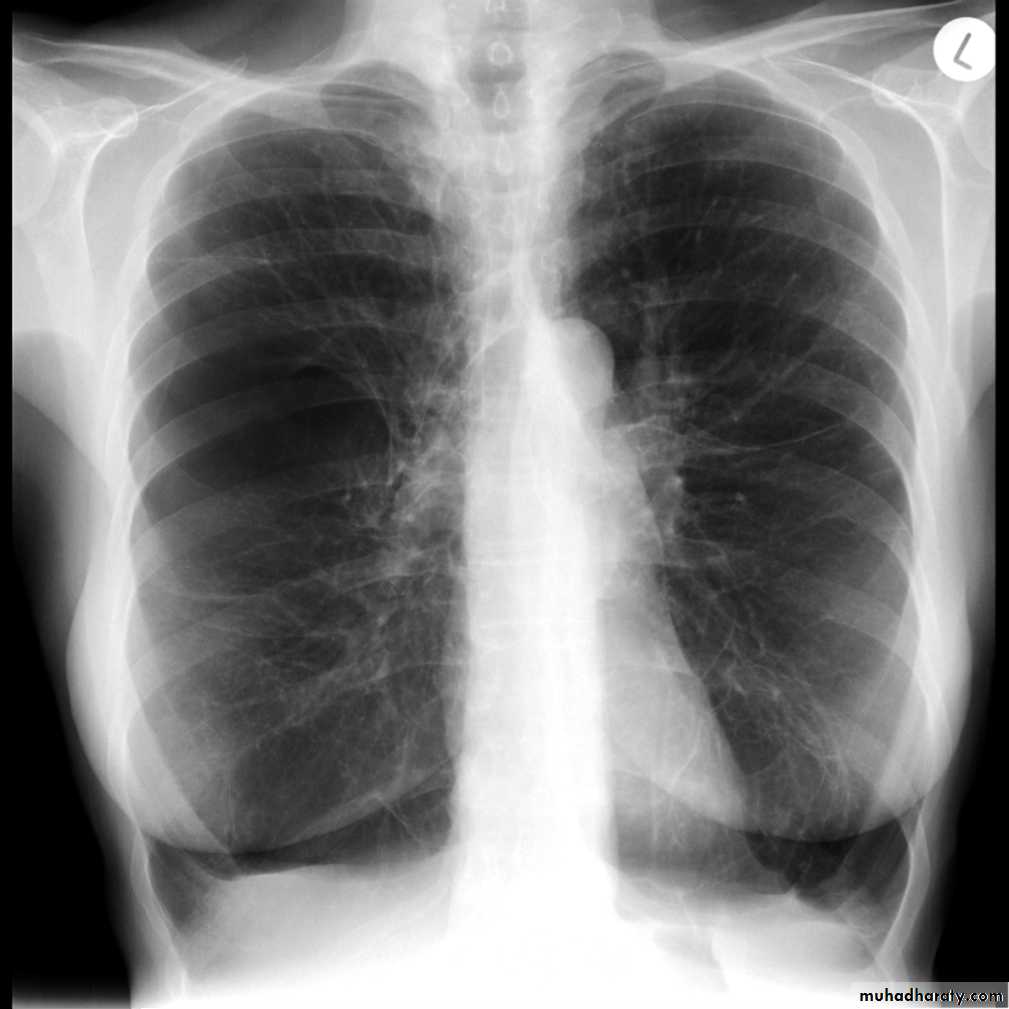

Left upper lobe collapse has distinctive features but can be challenging to identify on chest radiographs by the uninitiated.

Radiographic features

The left upper lobe collapses anteriorly becoming a thin sheet of tissue apposed to the anterior chest wall, and appears as a hazy or veiling opacity extending out from the hilum and fading out inferiorly . It thus reverses the normal slight increase in radiographic density seen as you move down the lung (due to increased thickness of the chest soft tissues).

Parts of the normal cardiomediastinal contour may also be obliterated where the left upper lobe, particularly the lingula abut the left heart border. The anterior parts of the aortic arch are also often obliterated from view.

In some cases the hyperexpanded superior segment of the left lower lobe insinuates itself between the left upper lobe and the superior mediastinum, sharply silhouetting the aortic arch and resulting in a lucency medially. This is known as the luftsichel sign.

The left hilum is also drawn upwards, resulting in an almost horizontal course of the left main bronchus and vertical course of the left lower lobe bronchus.

Non-specific signs indicating left sided atelectasis will also be present, including:

elevation of the hemidiaphragm

'peaked' or 'tented' hemidiaphragm: juxtaphrenic peak sign

crowding of the left sided ribs

shift of the mediastinum to the left

On lateral projections the left lower lobe is hyperexpanded and the oblique fissure displaced anteriorly. There is associated increase in the retrosternal opacity.